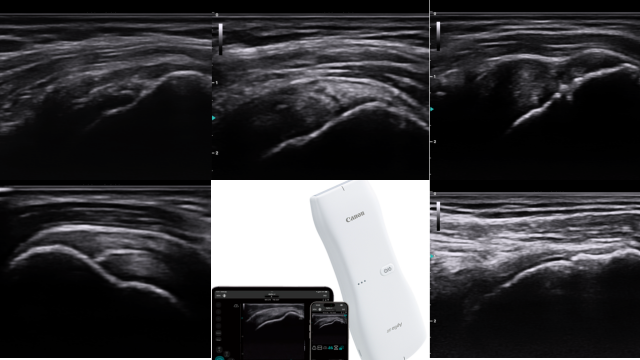

症状はもちろんのこと姿勢や動作も確認し、エコーを使って痛みの原因を観察します。体の柔軟性や筋力の偏り、骨の形状、体のバランスなどが原因となって、障害が発生することがあります。体トータルでの確認が大切です。